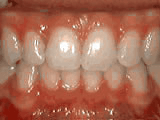

Open bite - Front teeth don't touch

Patient sucked her thumb as a young child. She started treatment at age 13. She had braces and a special appliance — called a crib — to retrain the tongue, for 28 months. Now she can bite the lettuce out of a sandwich.